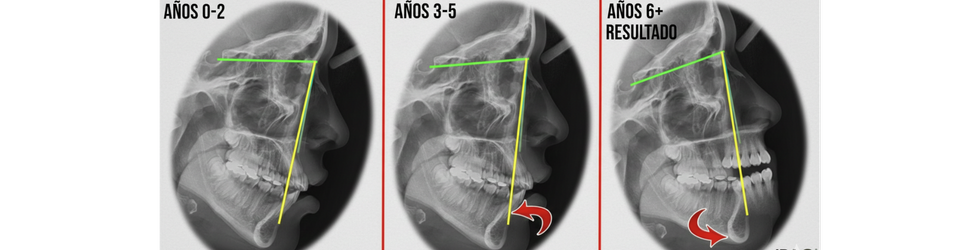

El gran valor de esta disciplina radica en el factor tiempo. Los huesos faciales de un niño poseen una plasticidad y suturas abiertas que se pierden irremediablemente al llegar a la edad adulta.

Un diagnóstico temprano de una Clase II (mandíbula retraída) o una Clase III (hipoplasia maxilar o prognatismo mandibular) permite al clínico intervenir con aparatología específica —como disyuntores, máscaras faciales o aparatos funcionales— para redirigir o estimular el crecimiento óseo.

Si dejamos pasar esta ventana de oportunidad, lo que podría haberse resuelto con ortopedia dentofacial de manera conservadora, a menudo termina convirtiéndose en un complejo caso de camuflaje dental (extracción de premolares para compensar) o, en situaciones severas, requiere una cirugía ortognática al finalizar el crecimiento.